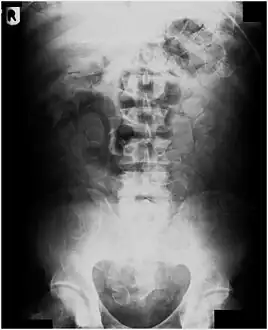

Plain radiograph of the abdomen of a drug "mule" showing drug capsules

Abdominal X-ray showing swallowed packages of cocaine.

Routine detection of the smuggled packets is extremely difficult, and many cases come to light because a packet has ruptured or because of intestinal obstruction. Unruptured packets may sometimes be detected by rectal or vaginal examination, but the only reliable way is by X-ray of the abdomen. Hashish appears denser than stool, cocaine is approximately the same density as stool, while heroin looks like air.[11][12]